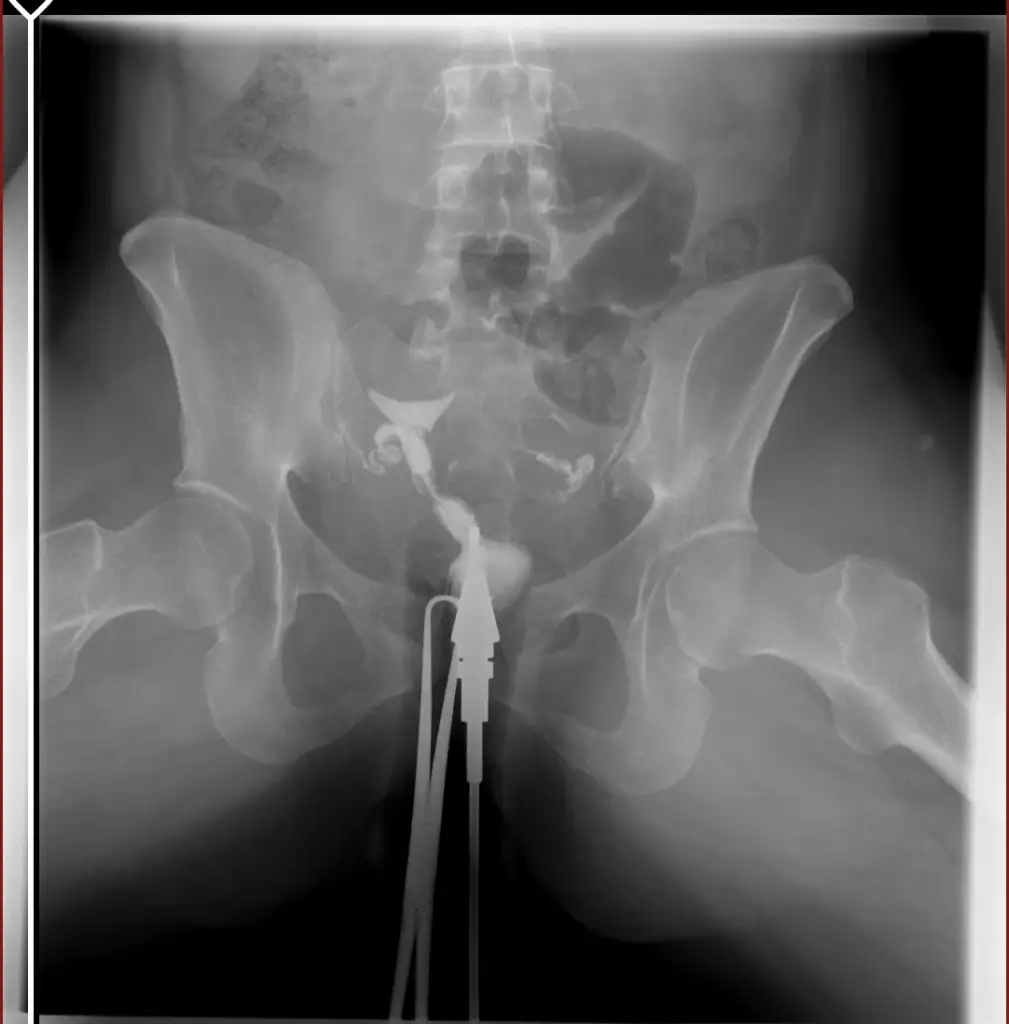

tüp bebek merkezine yönlendirdi . Orada daha detaylı kan tahlili muayene yapıldı adet bitimi hsg çekindim . Çekindiğim gün işlem başında doktor iki tüpün de tıkalı canım dedi ben ağlamaya başladım ağlama sakinleş ilaç ile açmaya çalışacağım eğer olmazsa ameliyat olursun demişti . İşleme 4-5 kez tekrarladık . Sonra iyi kötü bi gidiş oldu . O zaman ki ilgilenen doktora olanları anlattım böyle birşey imkansız tüpler açık o ara kasmışsındır dedi ama hiç kasmadım inanın ki . 6 ay dene olmazsa gel dedi 6 ay sonra gittim o doktor yoktu . Başka doktora geçtim oda sızıntının yeterli olmadığını hala tıkalı olduğunu ve içeriye iyi bir müdahale yapılması gerektiğini söyledi . Ameliyat önerdi . Laparoskopi olacağım ayın 27 sinde . Sonrasında aşılama yapmaya başlıcaz olmazsa